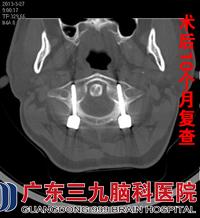

予以颅骨牵引制动,正规药物抗结核治疗,1个月后症状有所缓解,进一步证实了医生的诊断,行颈椎后路减压复位枕颈融合椎根弓钉棒系统内固定手术治疗。术后继续抗结核治疗病情明显好转。2013年3月27日复查颈椎CT示内固定术后改变,环枢关节间隙正常,齿状突低密度影消失,骨质破坏已修复。现随访至术后10个月,颈痛消失,无头胀,无饮水呛咳,四肢感觉肌力正常,活动良好。

CT是早期诊断极有效的方法,CT能清晰地显示骨的破坏和软组织肿胀影,尤其是在早期,能显现较局限的病变,结合病史,考虑为枢椎齿状突结核,行抗结核治疗,颅骨牵引10天后改头颈胸支具固定,加强营养支持治疗,主诉颈痛症状缓解。于2012年6月14日在全麻下行颈椎后路减压复位枕颈融合椎根弓钉棒系统内固定手术治疗,术后复位固定良好,出院后继续行抗结核治疗。10个月后复查CT示颈椎内固定术后改变,环枢关节间隙正常,齿状突低密度影消失,骨质破坏已修复。患者已无头颈部胀痛、饮水呛咳等症状,四肢感觉肌力正常,活动正常。www.999brain.com